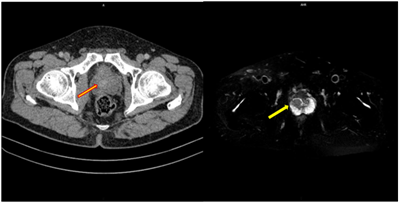

Case lâm sàng: Ứng dụng trí tuệ nhân tạo (Artificial intelligence – AI) trong chẩn đoán và điều trị sớm Ung thư phổi tại Trung tâm Y học hạt nhân và Ung bướu, Bệnh viện Bạch Mai

Theo GLOBOCAN 2022, ung thư phổi đứng đầu về số ca mới mắc (2.480.301 ca mới mắc chiểm 12.4%) và dẫn đầu số ca tử vong (1.817.172 ca tử vong chiếm 18.7%) trên toàn thế giới.  Tại Việt Nam tỷ lệ mắc ung thư phổi xếp thứ ba 13,5% lệ tử vong...